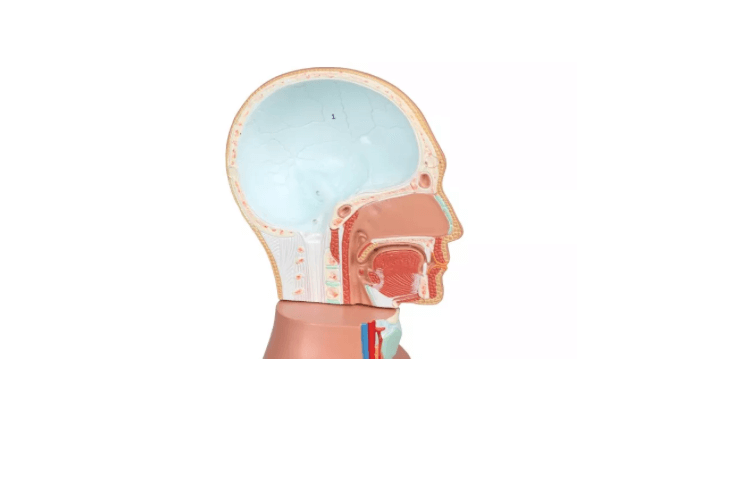

Grundkörper mit zwei Kopfhälften

Eine Kopfhälfte mit herausnehmbarem Gehirn